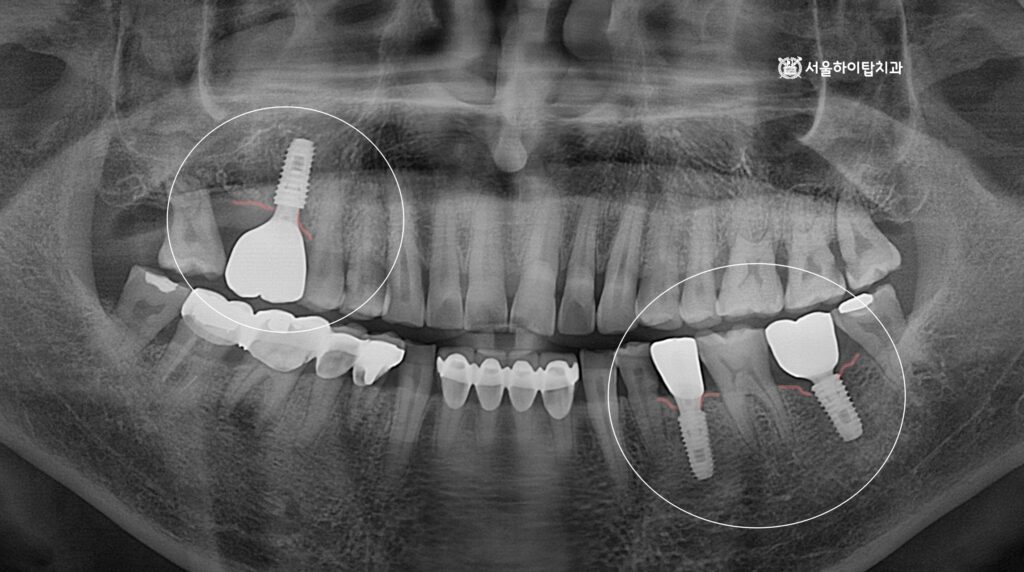

최종 결과

최종 보철은 지르코니아 크라운으로 제작되어 기능과 심미가 모두 회복된 모습입니다.

무엇보다 균등한 저작 환경이 만들어지면서,

앞니에 집중되던 과도한 저작 부담이 분산되고

전체 교합 안정성이 크게 향상되었을 것으로 보입니다.

이를 통해 장기적으로 마모나 교합 문제를 예방할 수 있는

보다 건강한 구강 상태가 완성된 모습을 확인할 수 있습니다.